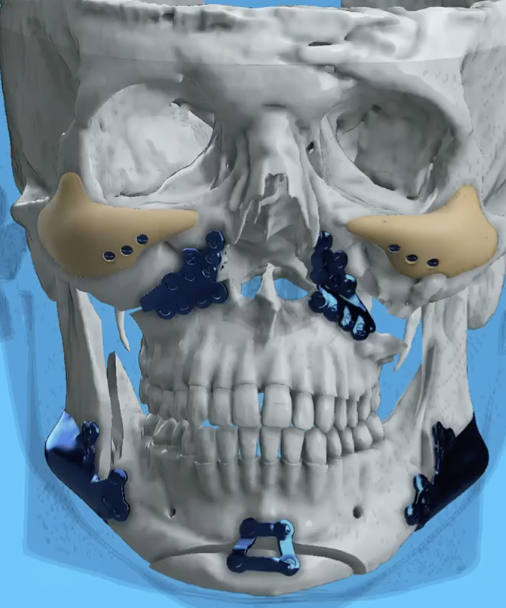

Take this Ramieri patient — very weak jaw, weak angularity — but then look at his results, and the rough design scan of his implant design:

now compare it to Clavicular’s plan for implants designed by GIANT:

as you can see, the result from the implant for this patient is very good, especially in the front. there is very good angularity, and basciall what you would want from a jaw implant

I bring this up because compared to Clavicular’s implant design, it is very conservative.

Take this Ramieri patient — very weak jaw, weak angularity — but then look at his results, and the rough design scan of his implant design:

now compare it to Clavicular’s plan for implants designed by GIANT:

as you can see, the result from the implant for this patient is very good, especially in the front. there is very good angularity, and basciall what you would want from a jaw implant

I bring this up because compared to Clavicular’s implant design, it is very conservative.